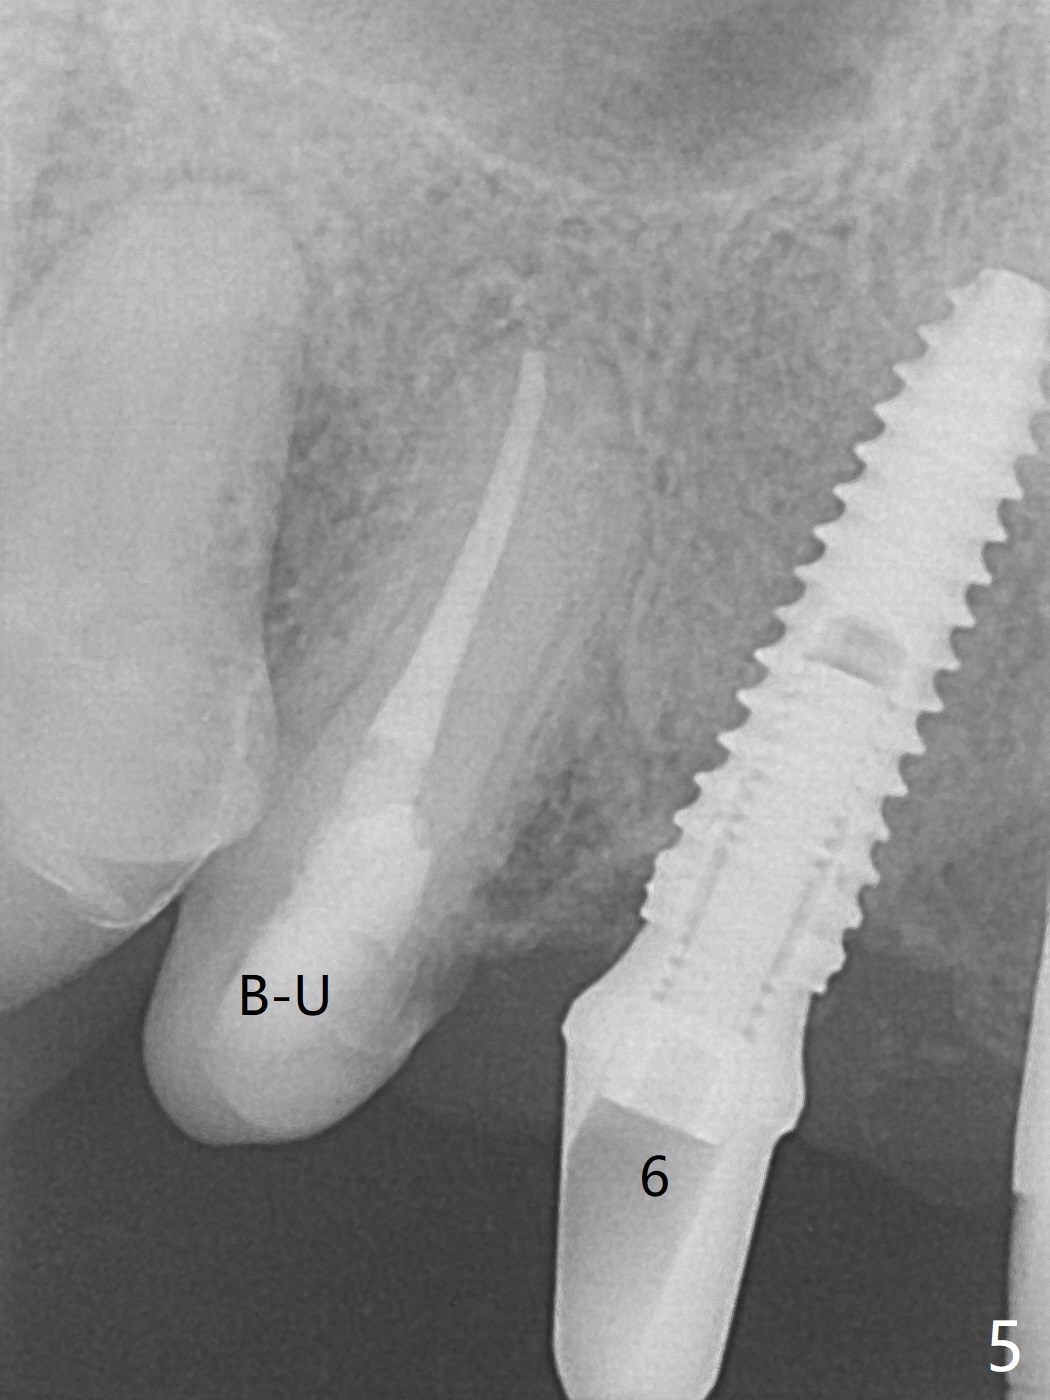

With temporarization of #3,4,13-15 (Fig.1), the anterior clearance is maintained (Fig.2). When provisional is removed, there is no papilla between #7 and 8 (Fig.3,4). After confirmation of complete seating of the abutments at #6 and 10 (Fig.5,6), gingivectomy is conducted with Diode laser (Fig.7,8). Following provisional being relined and modified, the anterior papillae form (Fig.9).